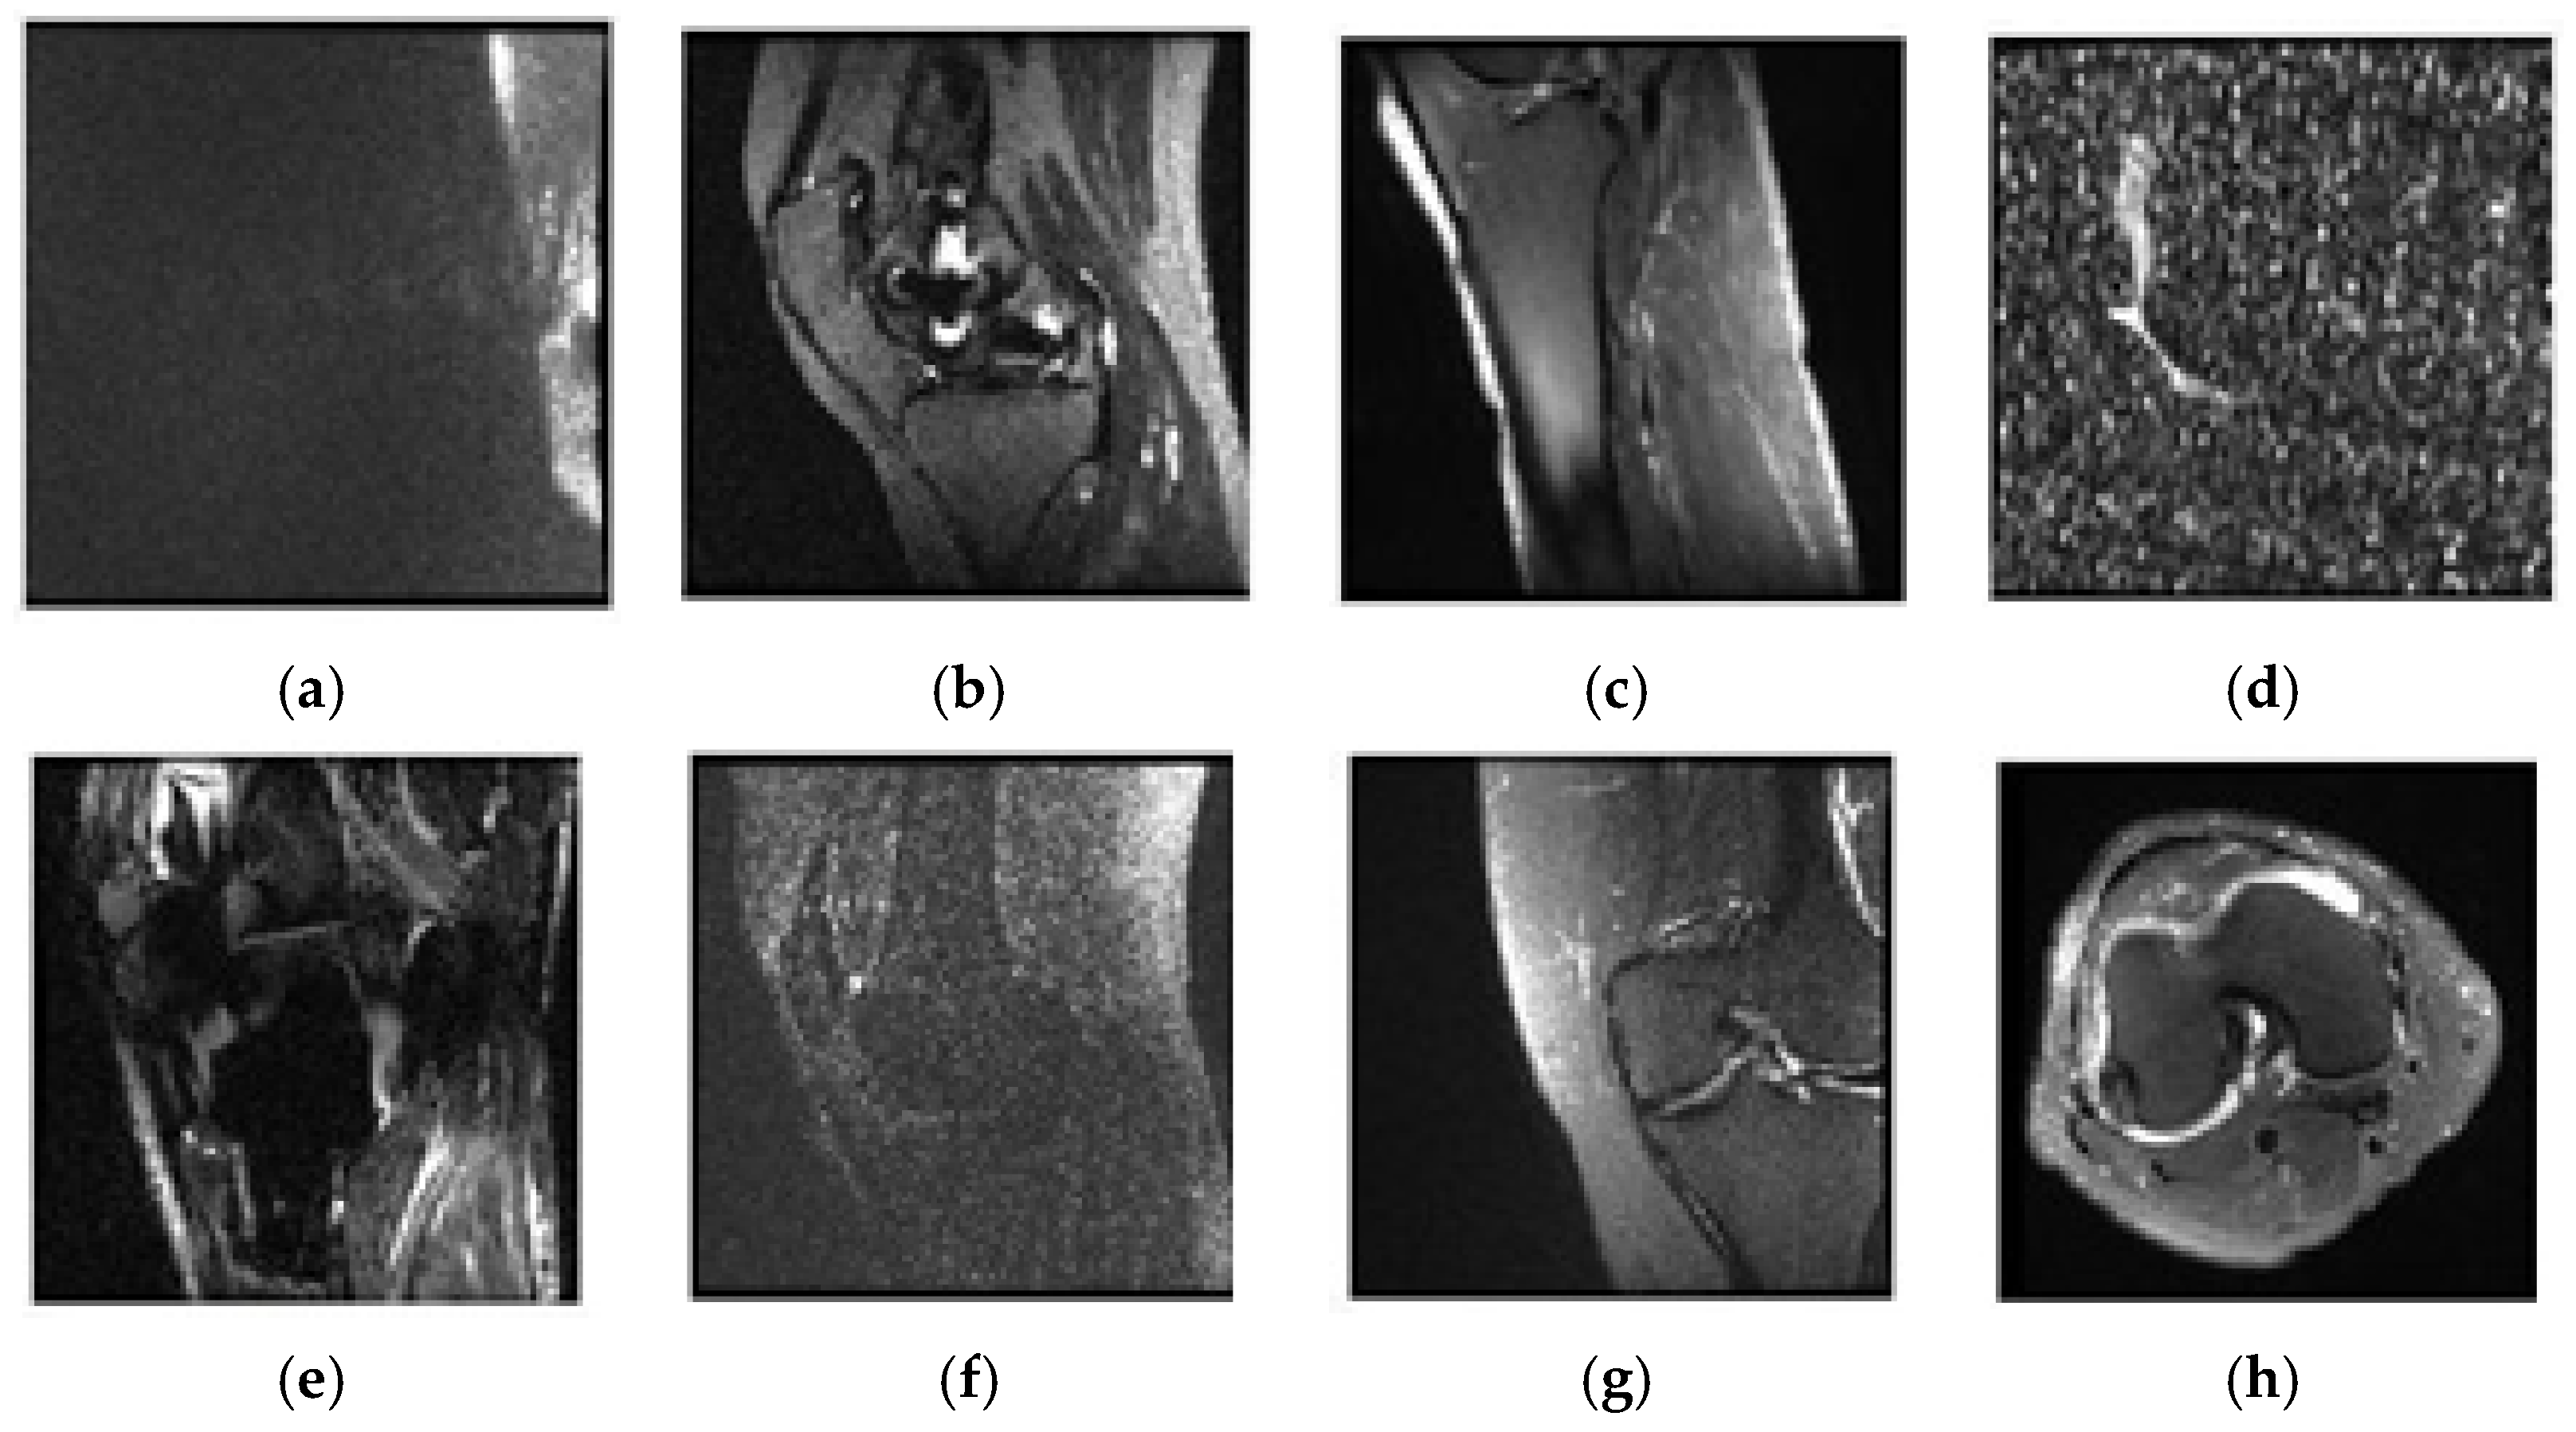

2.3. Selecting Eligible Data

2.3.1. Classification of Sagittal Images and Results

2.3.2. Classification of Coronal Images and Results

2.3.3. Classification of Axial Images and Results